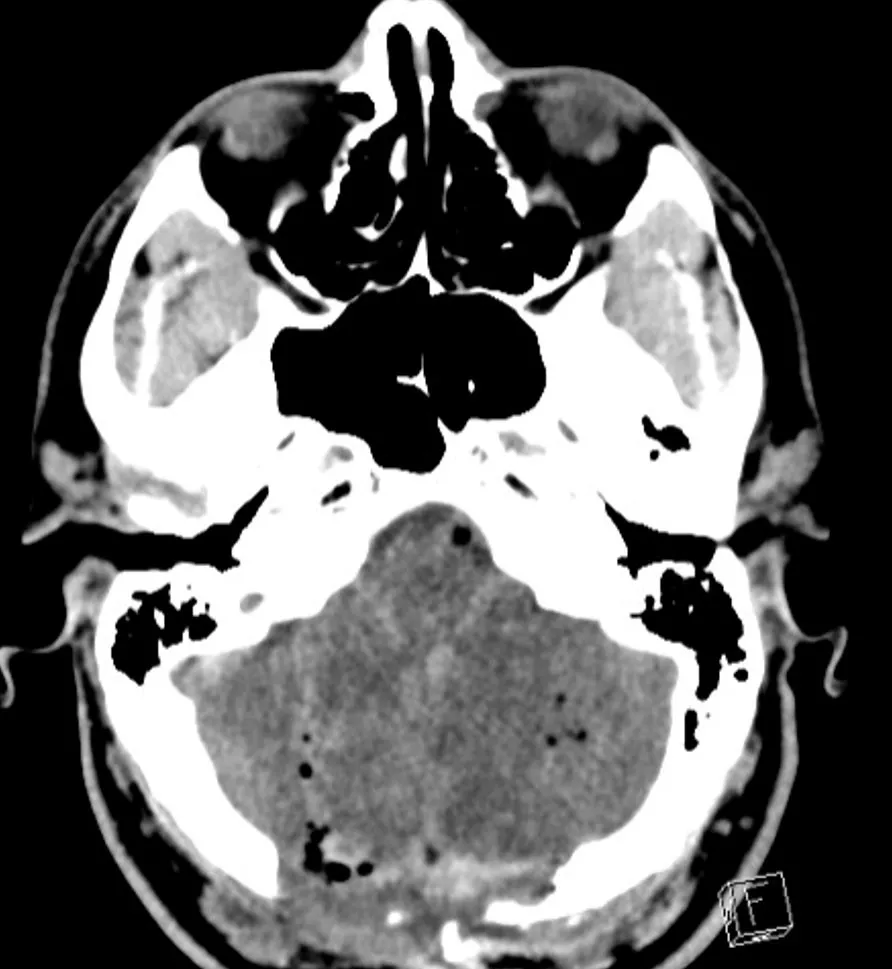

Approximately 12 hours after admission, the patient experienced a decline in his mental status, prompting a stat non-contrast computed tomography (CT) of the head which revealed bilateral cerebellar strokes. The associated cytotoxic edema resulted in significant mass effect on the 4th ventricle and early hydrocephalus.

Following the craniotomy, an emergent diagnostic angiogram was performed to evaluate for any residual thrombus of the basilar artery. The cerebral angiogram did not reveal a basilar thrombus but did confirm the aforementioned dissection. The patient was then placed on hypertonic therapy where he was monitored both clinically and with serial imaging. The patient was also monitored with continuous video electroencephalography (EEG) but no had no seizure activity.

Over the ensuing days, the patient's neurological exam improved, and after one week, he was able to be extubated. Follow-up imaging demonstrated improvement in the edema.